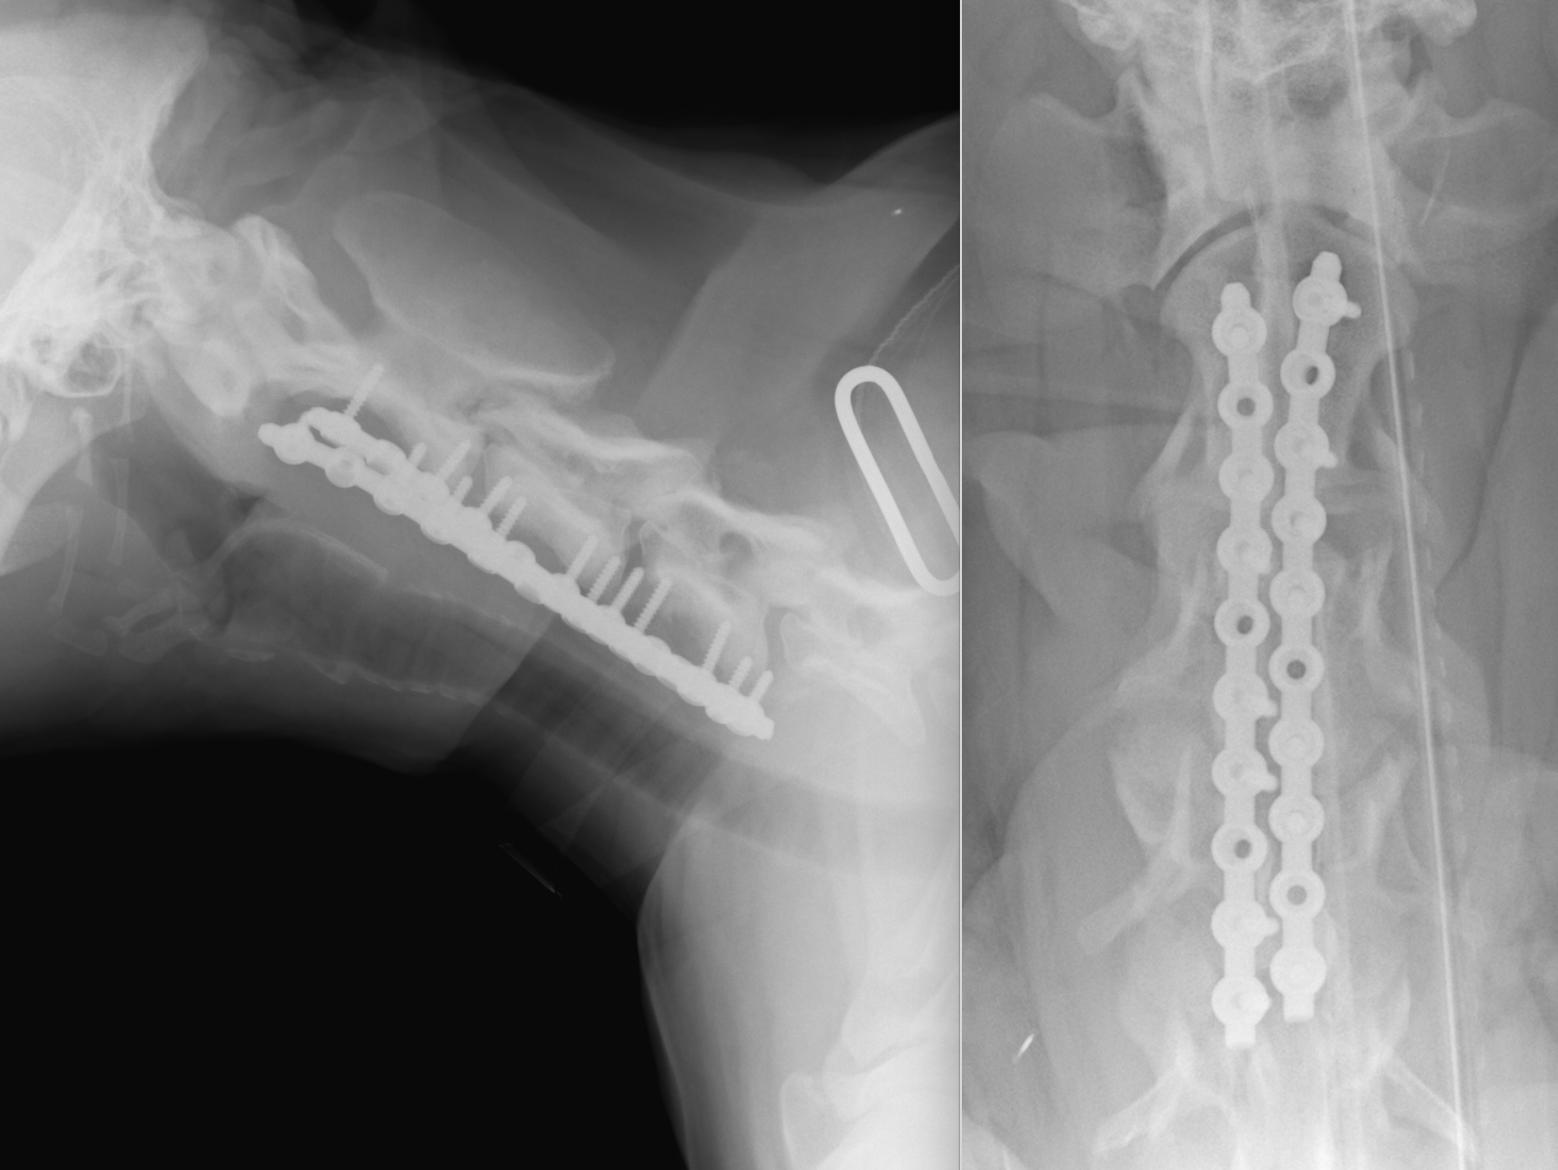

術後のX線画像検査です。

手術では計画を立てた位置で骨の切削を行い、減圧を実施し、同時に不安定性を解消するためにプレートによる固定を実施しました。骨の切削に4時間、固定に3時間かかり、すべてで8時間ほどの長時間の手術となりました。今回は責任病変が前方の2-3-4であろうと判断し、そこをメインに手術を実施しました。術後すぐの歩様動画です。術後はコルセットを装着しています。まだふらつきが残っている状態です。